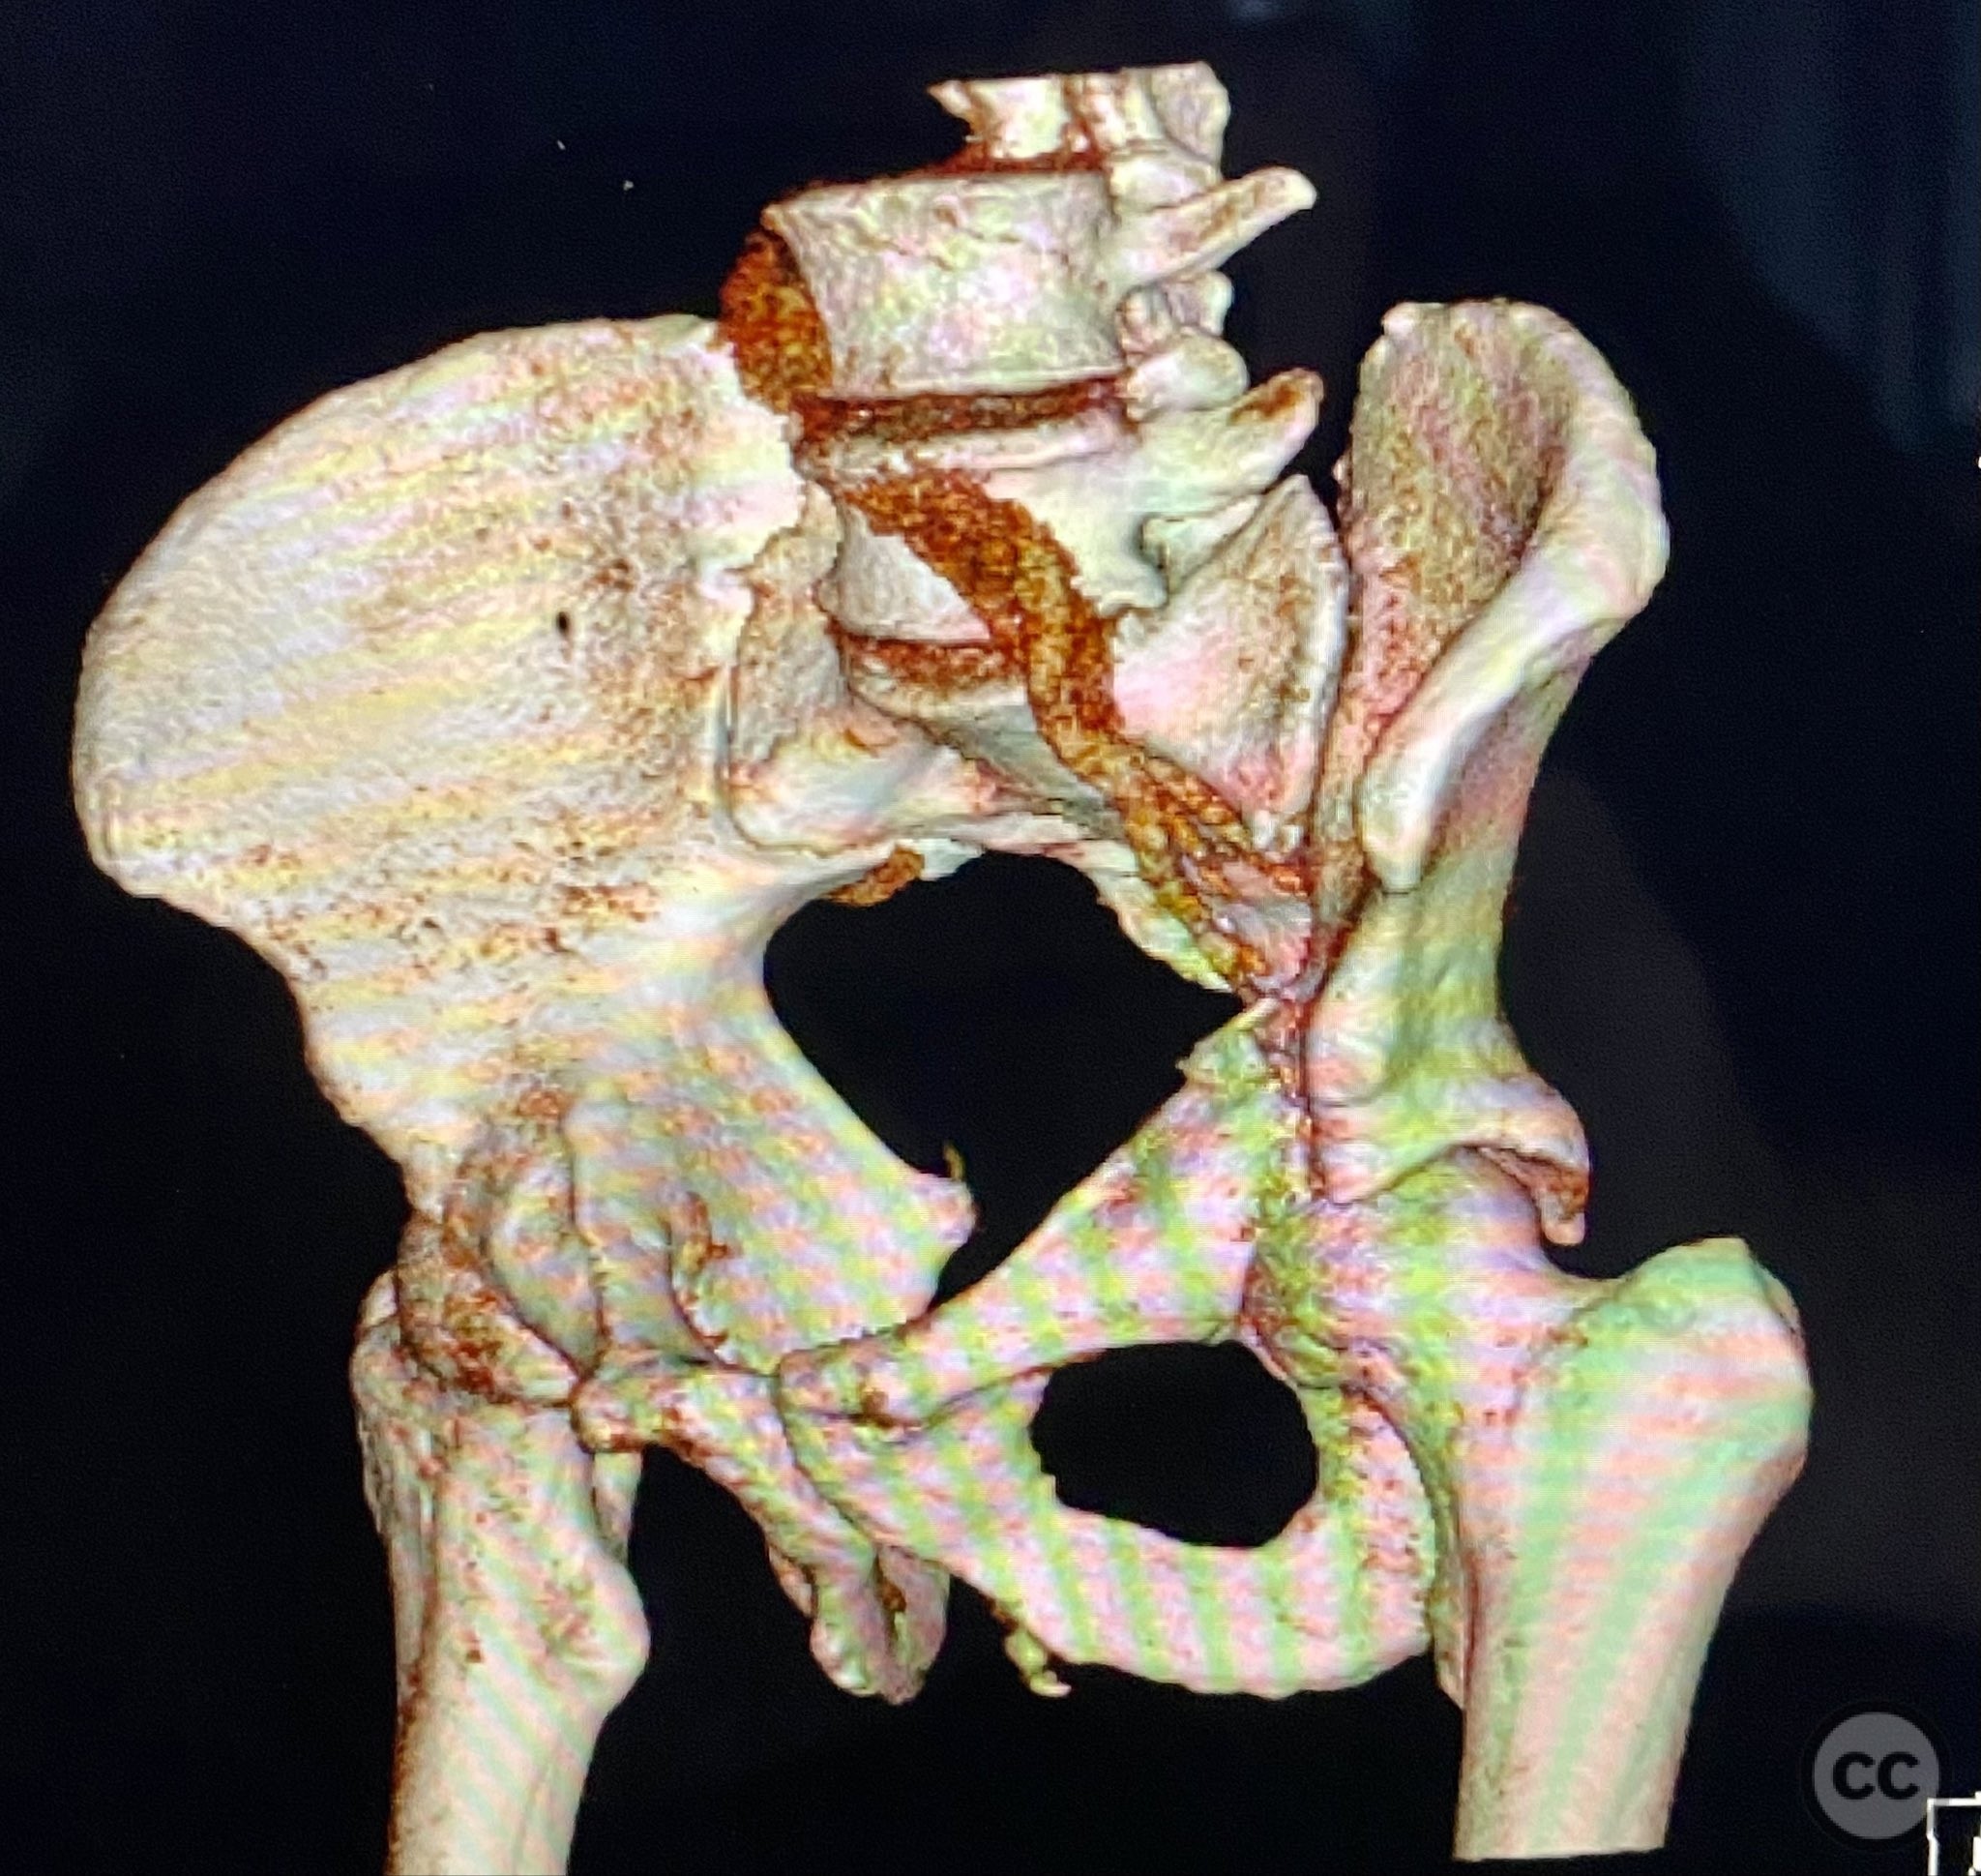

Clinical and radiological findings:  Adult male with a closed, comminuted left femoral shaft fracture and complex pelvic ring injury. Initial imaging demonstrated bilateral sacroiliac (SI) joint disruptions and a left-sided transtectal transverse acetabular fracture (Letournel-Judet: transverse type), with the fracture line exiting through the posterior wall region but without a discrete posterior wall fragment. The femoral head was displaced caudally, following the unstable distal acetabular segment, resulting in loss of congruency with the intact acetabular dome. There was also a symphyseal disruption. No associated abdominal, visceral, thoracic, cranial, or other injuries were present. Application of a circumferential pelvic binder resulted in visible changes in pelvic alignment on imaging. AO/OTA Classification: - Pelvic ring: 61-C1.3 (bilateral SI joint disruption, complete instability) - Acetabulum: 62-B1 (transverse fracture) - Femur: 32-C3 (comminuted diaphyseal fracture)

Preoperative Plan

Planning remarks:  The preoperative plan involved staged management: initial resuscitation and provisional stabilization with a circumferential pelvic binder, followed by operative reduction and fixation of the pelvic ring using an anterior two-pin external fixator for SI joint compression and reduction, percutaneous iliosacral (IS) and transsacral (TS) screw fixation, and subsequent intramedullary nailing of the femur. Definitive acetabular fixation was planned via a posterior Kocher-Langenbeck approach in the prone position.